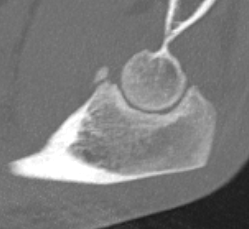

Elbow dislocation with radial head fracture

Based upon Mason classfication

Mason Classification

| Type 1 | Type II | Type III |

|---|---|---|

|

Minimally displaced fracture < 2 mm No block to rotation |

Displaced fracture radial head > 2 mm Reconstructable |

Comminuted fracture radial head Unreconstructable |

| Non operative |

ORIF + LCL repair / reconstruction +/- MCL repair / reconstruction if unstable |

Radial head replacement + LCL repair / reconstruction +/- MCL repair / reconstruction if unstable

|